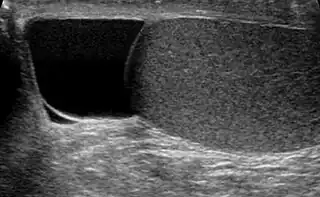

![]() Testículo (en gris) y espermatocele (en negro) | ||

Hallado indoloramente, la masa quística en la cabeza del epidídimo, con diafanoscopia se ve claramente diferenciado del testículo, y es generalmente suficiente. Si existe incerteza, la ultrasonografía de escroto puede confirmar si es espermatocele.